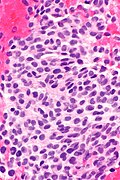

- Spindle cells without atypia and moderate lightly eosinophilic cytoplasm without distinctive cell borders.

- Eosinophilic matrix - described as "gungy" (shabby).[6]

- HPC-like vessels.

- Osteoclast-type giant cells.

- +/-Hemorrhage.

- +/-Calcifications.

- Phosphaturic mesenchymal tumour -- high mag.jpg

PMTMCT - high mag. (WC)